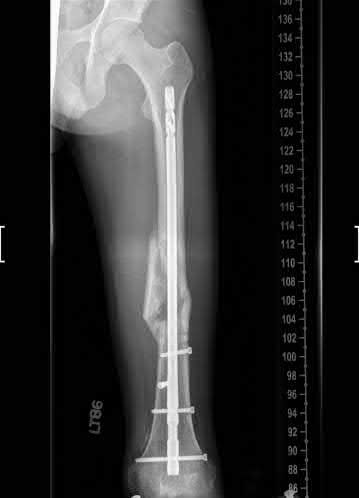

Question 17

A 32-year-old male sustains a closed tibia fracture and develops intense leg pain out of proportion to the injury. You suspect acute compartment syndrome.

Which of the following pressure parameters is considered the most reliable threshold indication for performing a four-compartment fasciotomy?

Explanation

The differential pressure (Delta P) is universally recognized as more reliable than absolute compartment pressure for diagnosing acute compartment syndrome. A Delta P is calculated by subtracting the intracompartmental pressure from the patient's diastolic blood pressure. A Delta P of less than 30 mmHg represents inadequate tissue perfusion pressure and is an absolute indication for emergency fasciotomy.